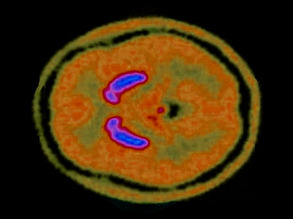

Dopamine Dip

Schizophrenia Awareness Week